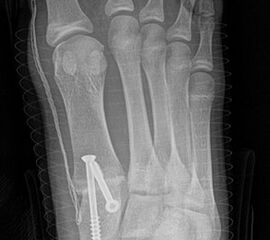

Röntgen

Standard ist die belastete Röntgenaufnahme des Fußes dorso-plantar und seitlich. Günstig ist eine Röhrenkippung von 10°-20°, um die Gelenke der Lisfranc-Linie einsehen zu können.

• Hallux valgus Winkel

• Intermetatarsalwinkel I zu II

• Pes metatarsus adductus